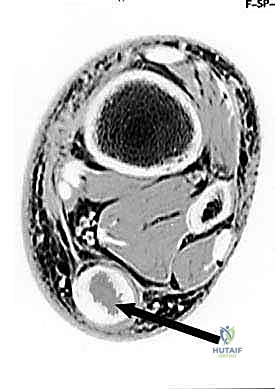

- التصوير بالرنين المغناطيسي (MRI): يُعد المعيار الذهبي لتقييم الأنسجة الرخوة. يوضح الرنين المغناطيسي مدى تدهور نسيج الوتر، وجود تمزقات جزئية غير ظاهرة، حجم الالتهاب في الجراب الزلالي، ويساعد الجراح في التخطيط الدقيق للعملية الجراحية.